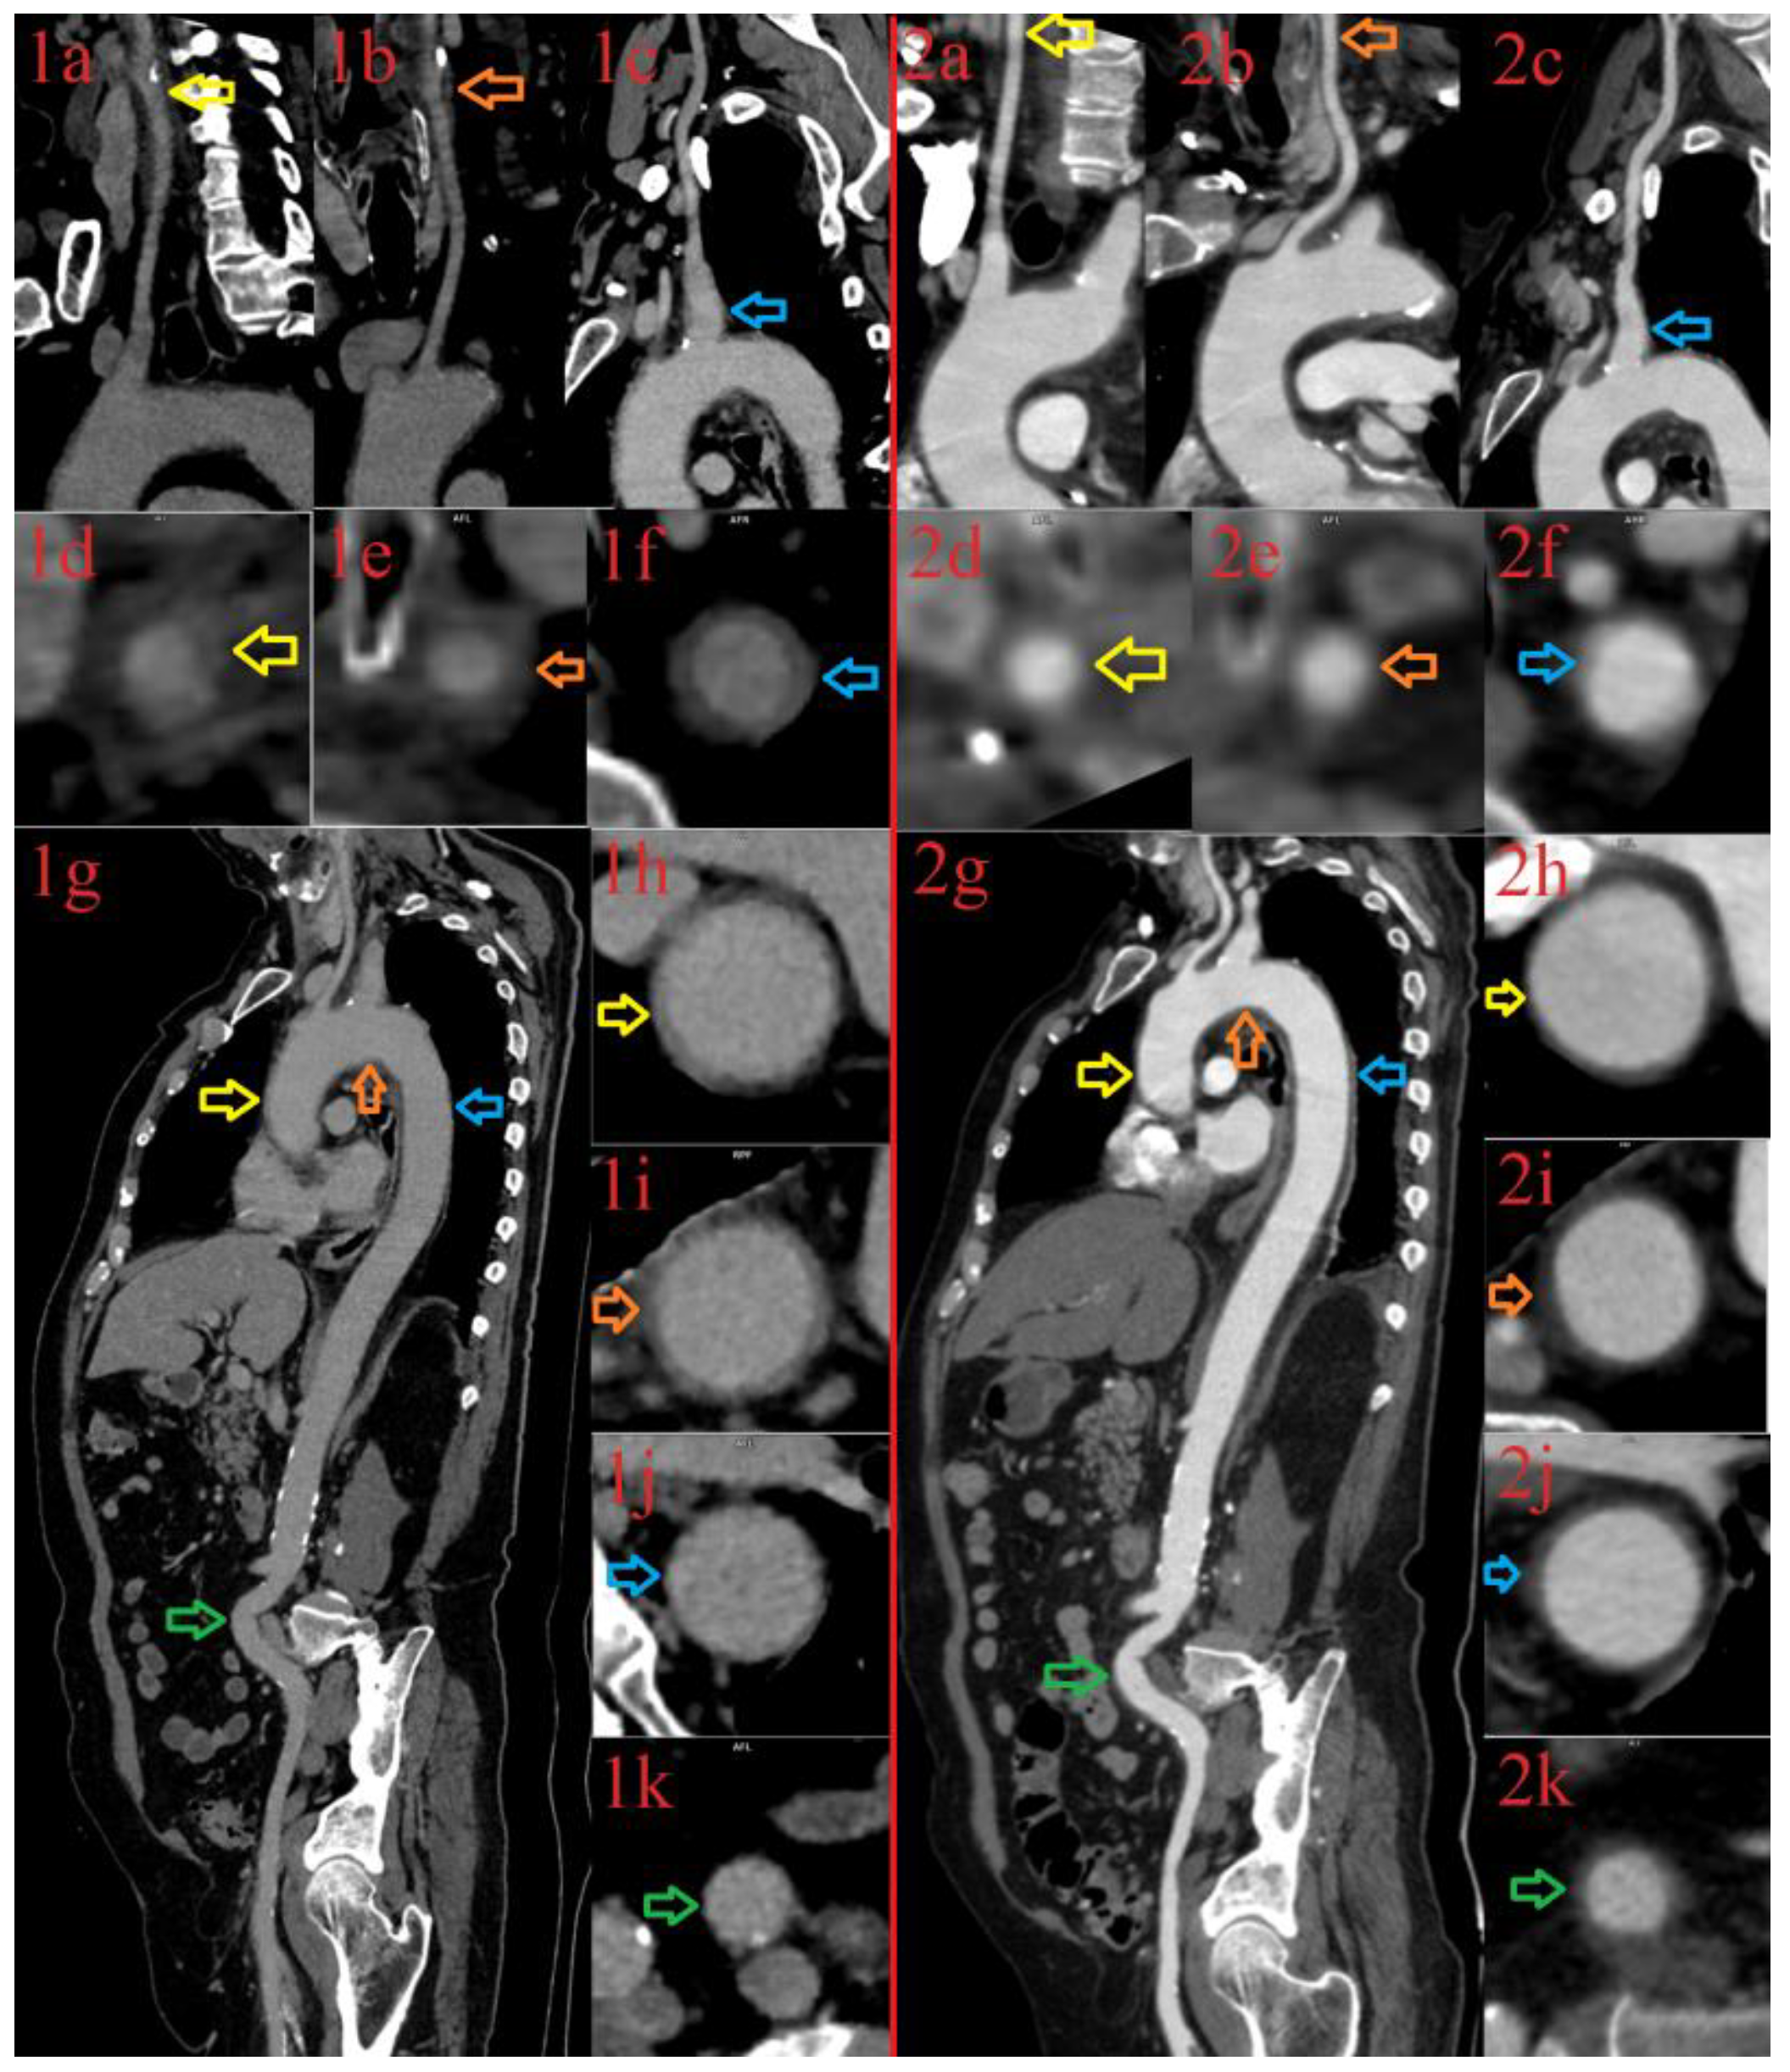

| Author | Age/Sex | Clinical Presentation, Laboratory Findings | Timing of Symptoms after COVID-19 | Diagnosis | Treatment | Testing | Outcome |

|---|---|---|---|---|---|---|---|

| Oda R, et al., 2020 [5] | 73 years, male | Persistent spiking fever, elevated ESR and CRP | concomitantly | LV-GCA | NSAID | CTA, FDG PET-CT | Recovered without treatment |

| Riera-Marti N, et al., 2021 [22] | 50 years, male | High fever, headache, temporal artery thickening, TM joint pain | concomitantly | c/LV-GCA | No treatment | Doppler US FDG PET-CT | Recovered without treatment |

| Jonathan G, et al., 2021 [7] | 47 years, male | PAAM, headache, jaw claudication | 8 weeks | PAMM TAB–negative GCA | High dose CS Tocilizumab | Ophthalmic diagnostic tests, TAB | Improvement on treatment |

| Ivanovic J, et al., 2022 * [8] | 69 years, male | Headache, fever, elevated ESR, CRP, Fib, IL-6 | 6 weeks | LV-GCA Cerebral vasculitis | High dose CS, TPE Tocilizumab, IVIG, AZA | FDG PET CT Brain MRI | Improvement on treatment |

| Aryal B, et al., 2022 [20] | 72 years, female | Headache, blurred vision, transient vision loss, abdominal pain | 8 weeks | TAB-negative GCA | High dose CS, AZA, MTX | Clinical presentation Laboratory tests | Improvement on treatment |

| Szydełko-Paśko U, et al., 2022 [6] | 69 years, female | Vision loss [left eye] Headache | 2.5 weeks | AAION c-GCA | High dose CS, MTX | Ophthalmic diagnostic tests | Improvement In treatment |